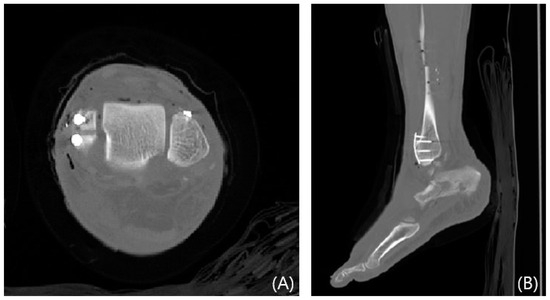

2.3. Radiological Evaluations

This study evaluated syndesmosis reduction by analyzing postoperative axial CT images captured 1 cm proximal to the tibial plafond (Table 1 and Figure 1) [16,17,18,19]. Four radiographic measurements were chosen and assessed with a PACS image viewer software (Dejaview2 version 1.0, Dongwun Information Technology, Republic of Korea). Two independent observers, blinded to patients’ clinical outcomes and current complaints, objectively evaluated the measurements. The process was repeated after a 6-week interval to ensure reliability.

Figure 8. Postoperative CT images showing mini-plate fixation for a Wagstaffe tubercle fracture. Axial (A) and sagittal (B) views.